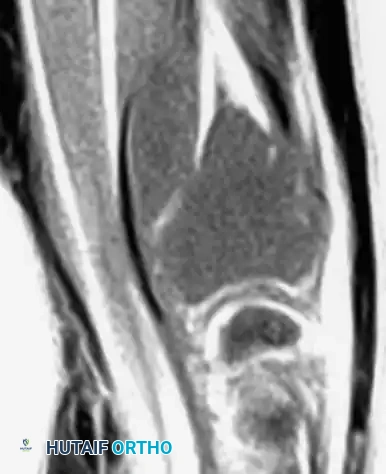

Advanced Imaging (MRI and CT)

Magnetic Resonance Imaging (MRI) is essential for evaluating the extent of the lesion, assessing articular cartilage integrity, and identifying secondary aneurysmal bone cysts (ABCs), which are present in up to 20% of patients. MRI typically reveals extensive bone marrow edema surrounding the lesion, which can be disproportionate to the tumor's size, further explaining the severe joint pain.

Computed Tomography (CT) is highly sensitive for detecting subtle intralesional calcifications and delineating the exact three-dimensional anatomy of the cortical margins, which is critical for planning the surgical approach and cortical window.